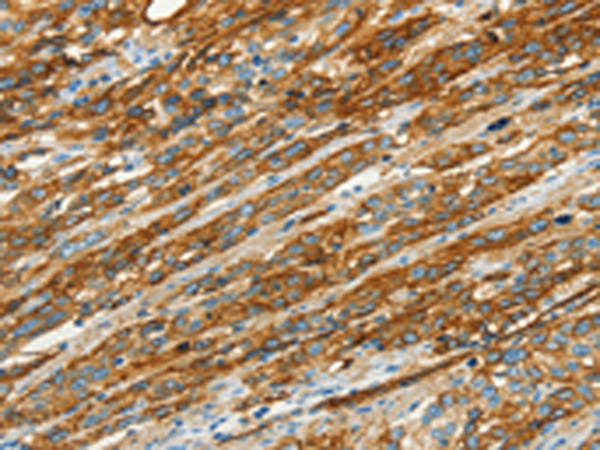

分类: 科研抗体货号: P04673别名: CGL3; PPH3; BSCL3; VIP21; MSTP085应用: WB,IHC反应种属: Human, Mouse, Rat